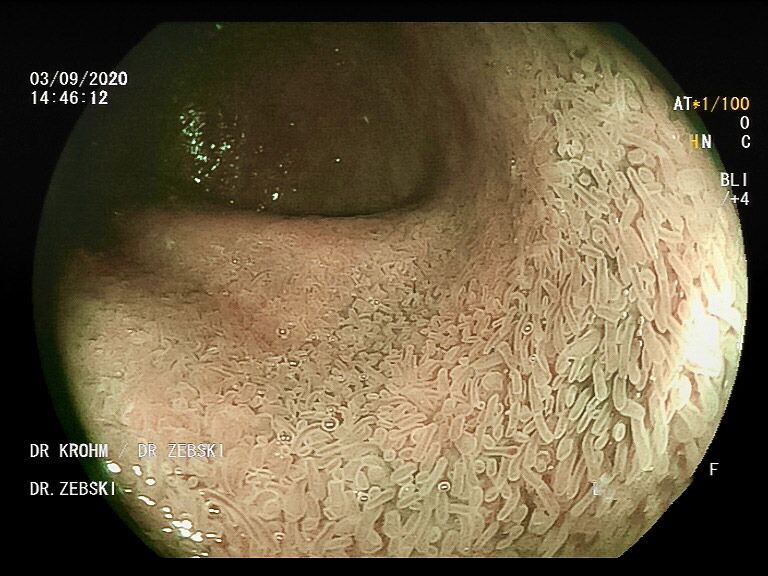

Die Darmspiegelung ist der uneingeschränkte Goldstandard für die Diagnostik und Vorsorge sämtlicher Erkrankungen des Dickdarms und des untersten Dünndarms. Die hochauflösende Bildqualität (High Definition) unserer modernen Videokoloskope ermöglicht eine zuverlässige Einordnung nahezu sämtlicher entzündlicher oder geschwulstiger Veränderungen der Dickdarmschleimhaut.

Die Darmspiegelung hilft, dass Darmkrebs gar nicht erst entstehen kann. Denn während der Untersuchung werden auch Polypen entfernt, aus denen sich der Darmkrebs in der Regel entwickelt. Von allen Maßnahmen zur Früherkennung dieser Polypen besitzt die Koloskopie die höchste Empfindlichkeit. Sie weist kleinste Polypen, aber auch Darmkrebs nach, der noch keinerlei Symptome macht. Die Abtragung dieser Polypen erfolgt direkt, wenn sie entdeckt werden. Das geschieht völlig schmerzfrei. Durch die Abtragung der Polypen kann die Entstehung von Darmkrebs effektiv verhindert und die krebsbedingte Sterblichkeit gesenkt werden.